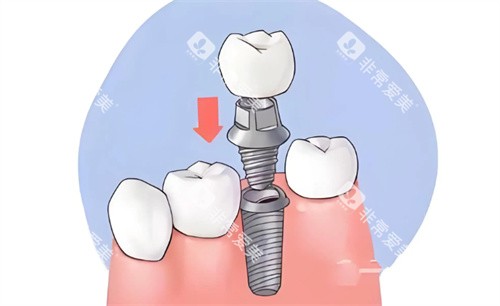

例如高岩石医生,作为优诺口腔哈尔滨地区的技术总监,擅长小创口智能化口腔种植技术、即刻种植技术等多种高难度种植技术;

以种植牙和正畸为例,有患者分享,在做诺贝尔种植牙手术时,护士会安慰紧张的患者,医生手法稳,手术时间短,术后修复快,第二天就能正常吃饭;正畸患者也表示,医生会制定详细的方案,复诊时耐心调钢丝,还会教导正确的刷牙方法。

种植牙患者做完手术后,牙齿稳固,吃东西不再有问题;